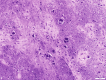

Phosphaturic mesenchymal tumors (PMT) are a rare neoplasm oftentimes associated with tumor-induced osteomalacia (TIO). The non-specific presentation and symptoms of these pathologies make them difficult to diagnose. We report a case of a 52-year-old patient with an intermetatarsal phosphaturic mesenchymal tumor who presented to the orthopedic sports medicine clinic with metabolic deficiencies and bilateral subtrochanteric cortical stress fractures indicative of osteomalacia. The tumor was entirely resected within nine months of symptom onset and has shown no recurrence at the one-year follow-up. This case report characterizes an unusual cause of stress fractures presenting to orthopedic sports medicine clinics and the variability in the presentation of phosphaturic mesenchymal tumors.